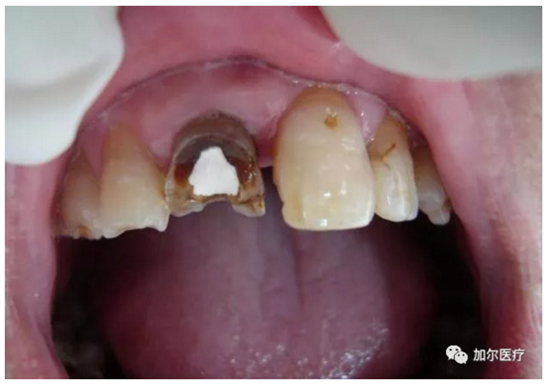

判斷牙齦上是否起膿包!

1、很遺憾地告訴你,一旦長(zhǎng)膿包說(shuō)明牙髓失去活力,甚至病變牙髓沉積在根尖部位刺激根尖周圍組織,瘺管受感染起炎癥后膿液流出,穿透牙槽骨起膿包,這種病髓就得抽出,清洗消毒髓腔以及根尖部位,并且還得封消炎藥。

2、其實(shí)說(shuō)的就是根管治療,只不過(guò)多了清理根尖部位,還有牙齦膿包位置的消炎殺菌,有些患者深度蛀牙引起牙痛,明明可以早點(diǎn)做根管治療,拖到病髓壞死發(fā)生根尖周炎,這時(shí)候再來(lái)治療還得加錢治根尖炎,結(jié)果反而更糟還要花更多錢!